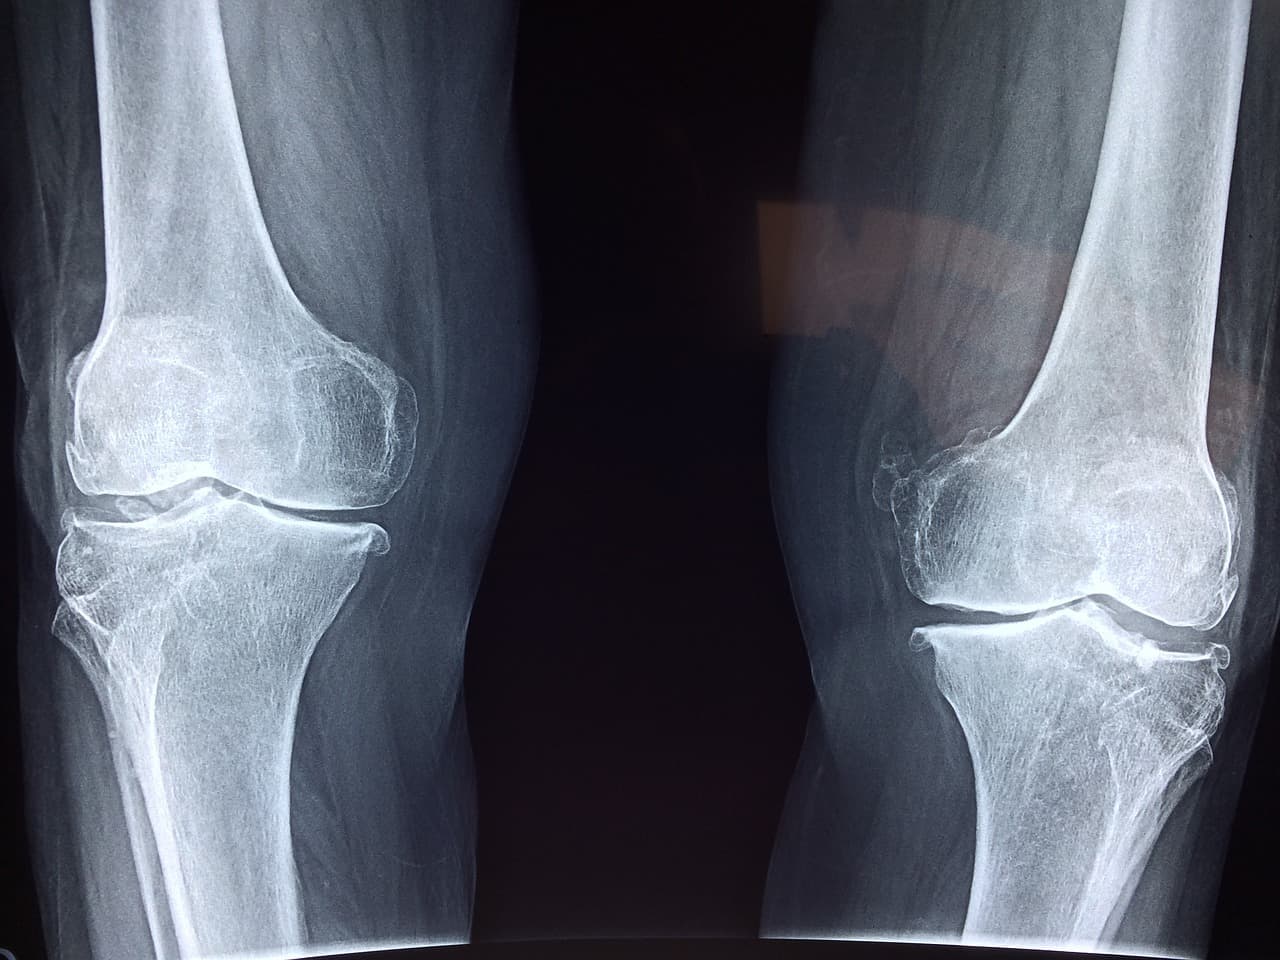

5. Oμν λ€λ¦¬μ 체ν λ³ν: μΈκ΄μΌλ‘ λλ¬λλ μ νΈ

λ¬΄λ¦ μ°κ³¨μ΄ νμͺ½μΌλ‘ λ³κ² λλ©΄ νμ€μ΄ λΉμ μμ μΌλ‘ λΆμ°λμ΄ λ€λ¦¬ ννμ λ³νκ° μκΉλλ€. νν λ§νλ **Oμν λ€λ¦¬(μΈλ°λ³ν)**λ μ°κ³¨ λ§λͺ¨κ° μ¬νλμμ λ λνλλ μ νμ μΈ μΈνμ λ³νμ λλ€. λ€λ¦¬ μ λ ¬μ΄ νμ΄μ§κ³ , 보ν μ μ€μ¬μ΄ ννΈλ¬μ§λ©°, κ· ν κ°κ°μλ μν₯μ μ£Όκ² λ©λλ€.

μ΄λ‘ μΈν΄ 보ν μμΈκ° λ°λκ³ , 골λ°μ΄λ ν리μλ λΆλ΄μ΄ κ°μ€λμ΄ 2μ°¨μ μΈ ν΅μ¦μ μ λ°ν μ μμ΅λλ€. μΌλΆ νμλ€μ λ€λ¦¬κ° νμ΄μ§λ©΄μ ν€κ° μ€μ΄λ κ² κ°μ μ°©κ°μ νκ² λλ©°, μ€μ λ‘ μμΈ λΆκ· νμΌλ‘ μΈν΄ μμΈκ° ꡬλΆμ ν΄μ§λ κ²½μ°λ μμ΅λλ€. μ΄λ¬ν λ³νμ λ¨μ λ―Έμ©μ λ¬Έμ λ₯Ό λμ΄μ κΈ°λ₯μ μΈ μ₯μ μ λ§μ± ν΅μ¦μ μμΈμ΄ λ μ μμΌλ―λ‘ λ°λμ μΉλ£κ° νμν©λλ€.